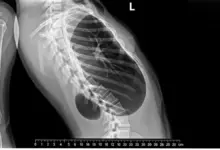

Alterações degenerativas da coluna cervical

Com o passar dos anos, é comum surgir desgaste nas articulações e discos do pescoço, quadro conhecido como espondilose cervical.

Em algumas pessoas, esse processo causa inflamação, compressão de nervos e dor que começa na cervical e alcança a cabeça.

Hérnia de disco cervical

Quando parte do disco entre as vértebras se desloca, pode comprimir raízes nervosas e estruturas ao redor.

O resultado é dor na região do pescoço, que muitas vezes acompanha irradiação para a cabeça, ombros e braços, formigamento ou perda de força.